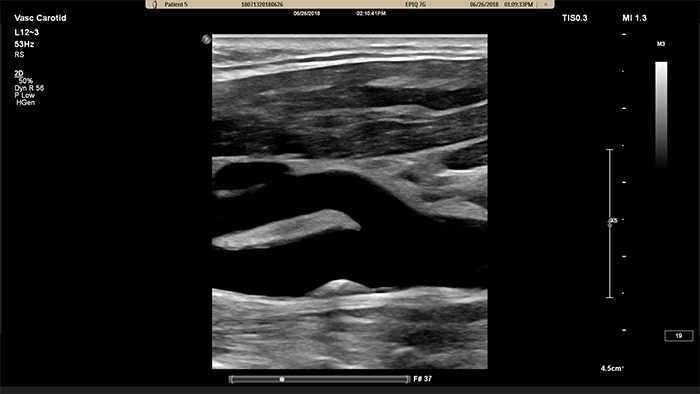

Le traitement nouvelle génération des images de Philips améliore l’imagerie vasculaire en offrant une superbe délimitation des interfaces vasculaires et une meilleure perception de la texture de plaque. En réduisant le flou dans les vaisseaux et les artefacts, XRES Pro améliore la fiabilité du diagnostic lors de la réalisation d’examens d’imagerie vasculaire chez les patients, y compris ceux qui sont techniquement difficiles.

MicroFlow Imaging de Philips est conçu pour détecter les flux de très faible vitesse et de petit calibre au sein des tissus, avec une sensibilité remarquable, et améliore la résolution du flux lors d’explorations vasculaires. Grâce à sa haute résolution et à son faible nombre d’artefacts, les cliniciens peuvent visualiser et caractériser des perturbations subtiles du débit autour d’une plaque sténosée afin d’établir des diagnostics fiables.